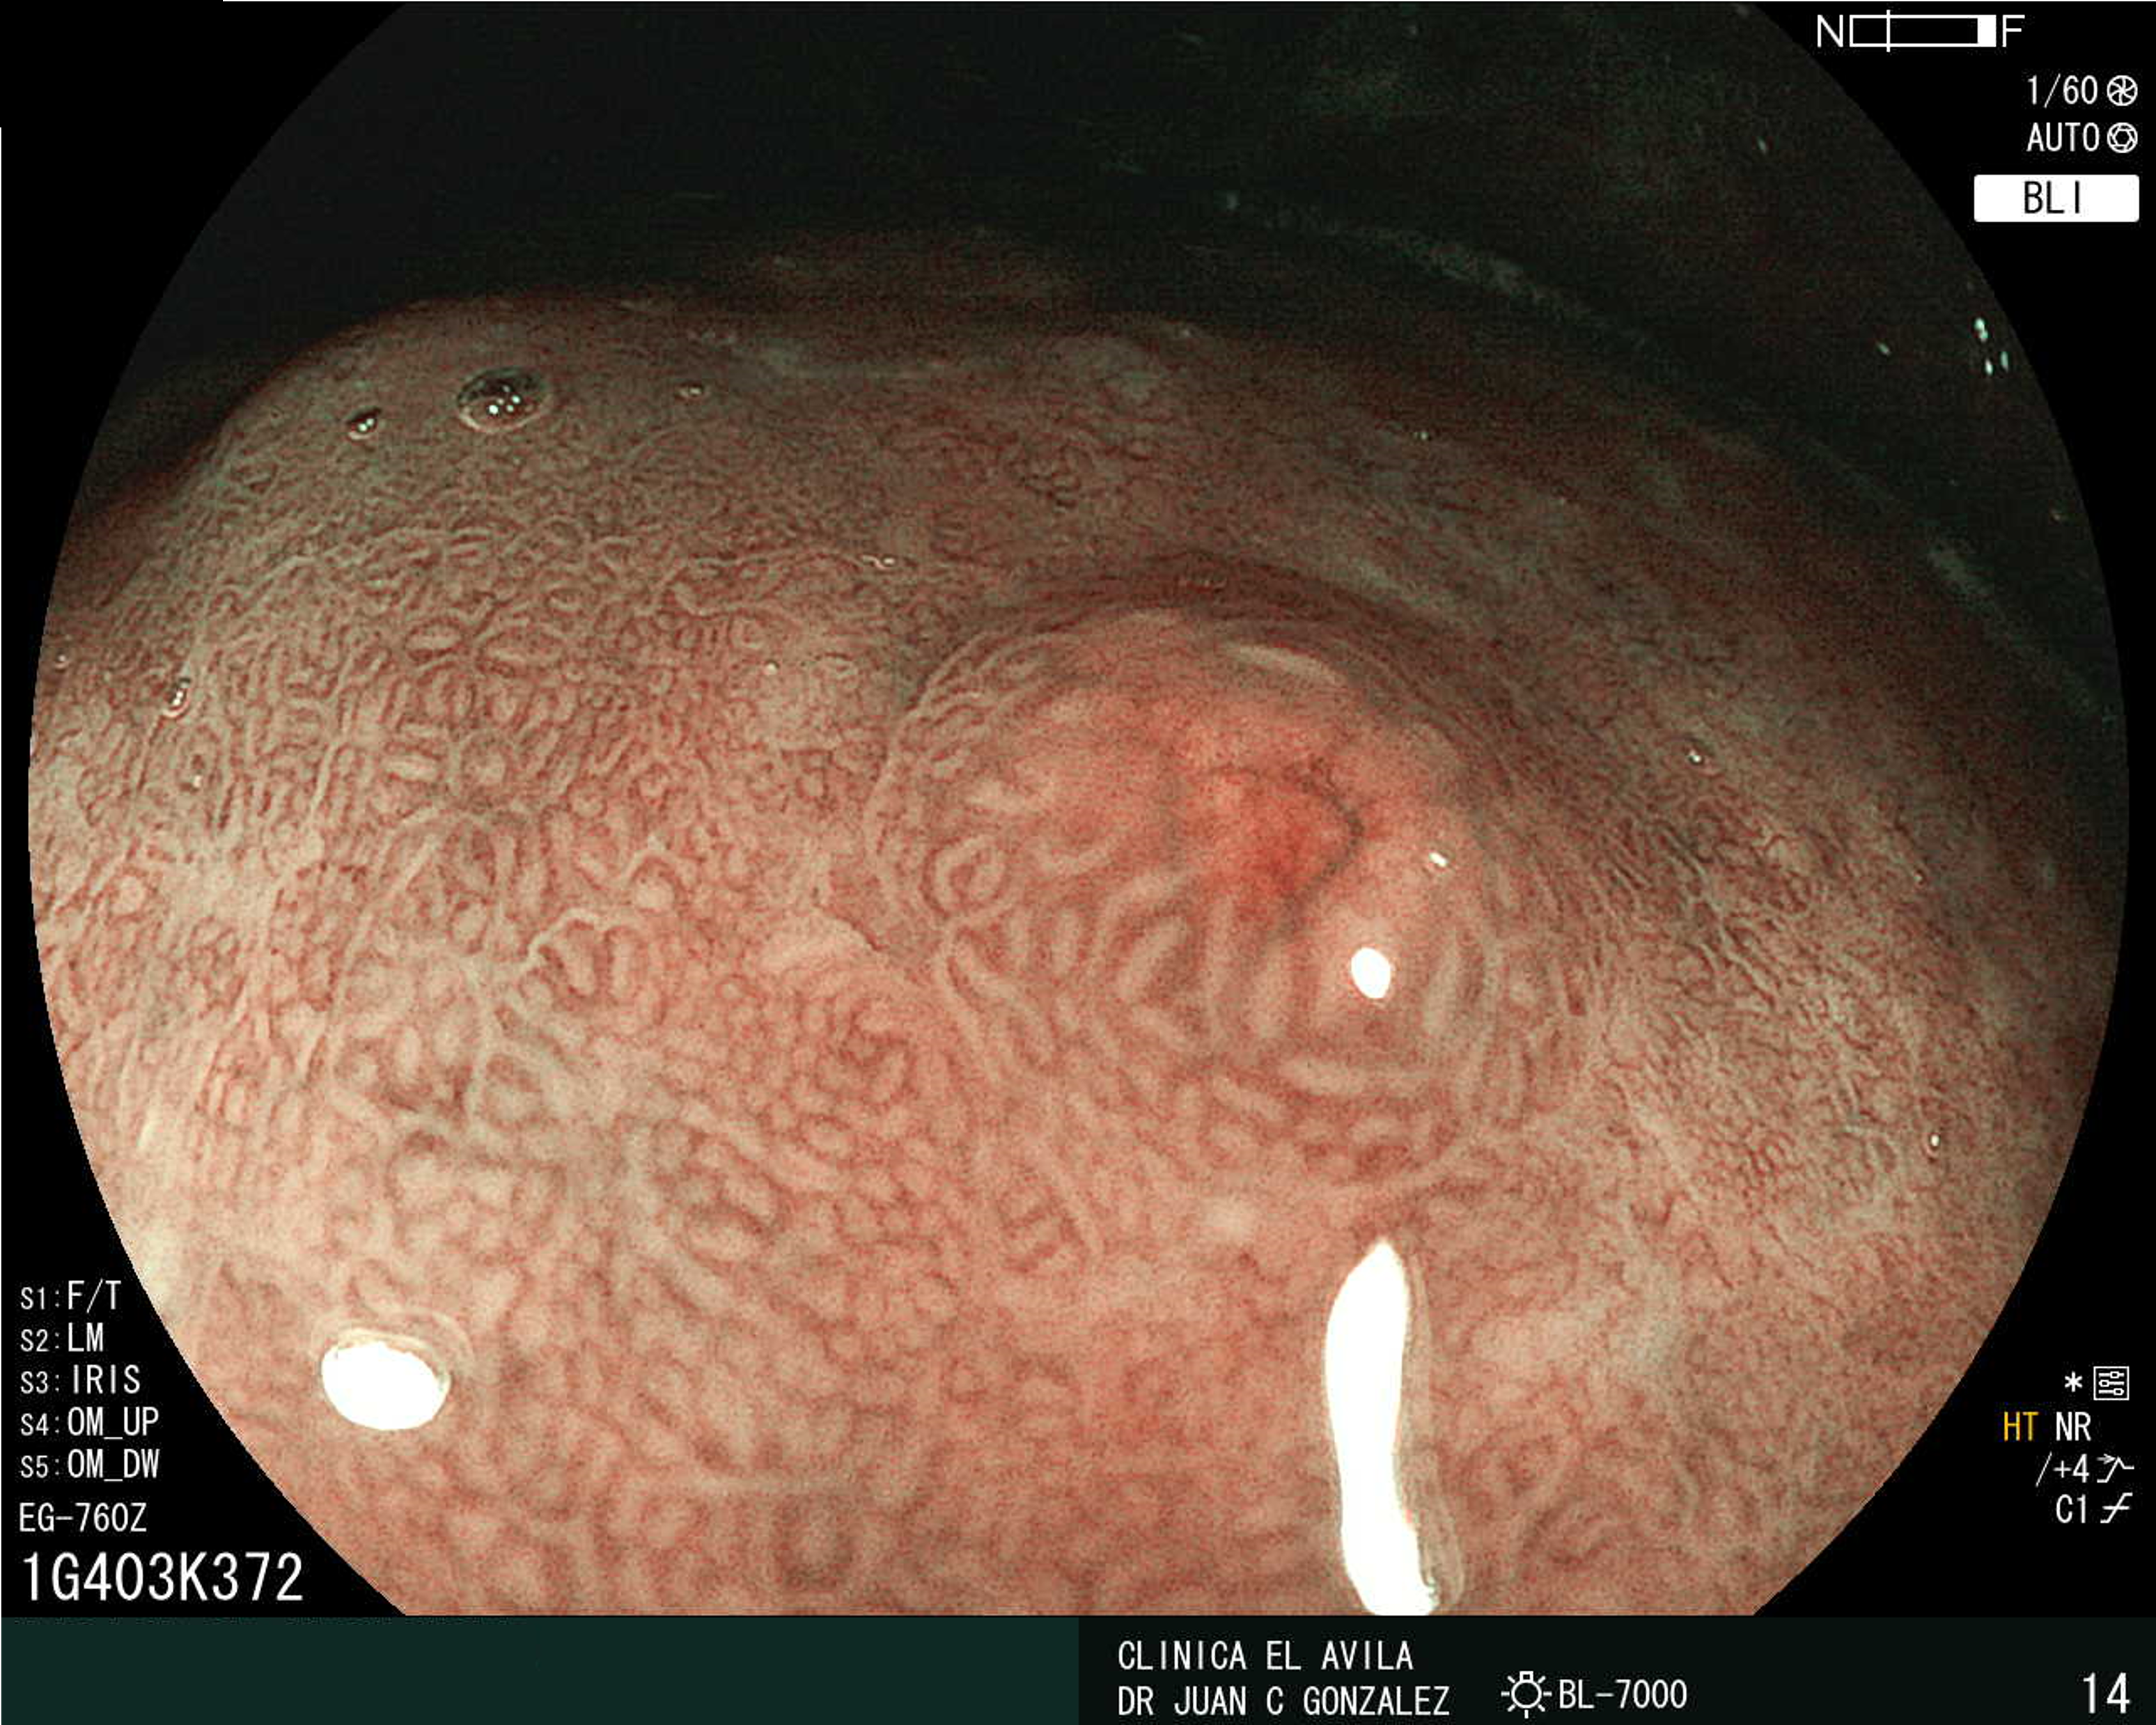

| Figura 1. Tumor Neuroendocrino Gástrico | Figura 2. Hiperplasia de Células Neuroendocrinas en estómago |